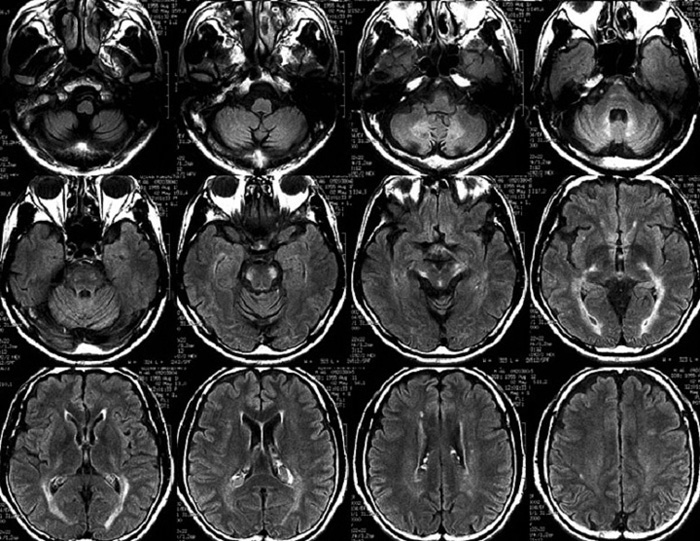

症例4:46歳、男性

歩行困難、 下肢の脱力

約15年前から両下肢の動かしにくさ、歩きにくさを自覚するようになった。その後徐々に増悪し、現在は杖なしでは歩行できない。

WASI-Rにてtotal IQ 74。

図3 FLAIR